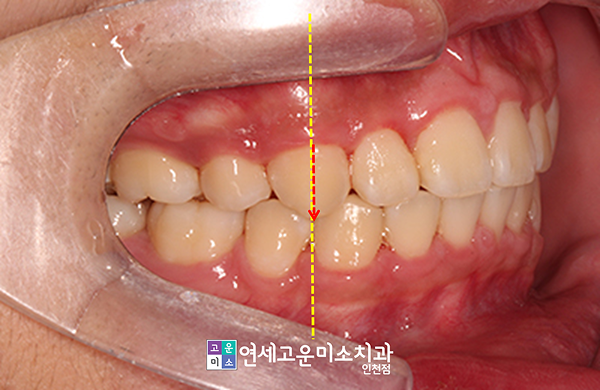

상악이 약간 앞으로 나온 무턱 경향을 보이고 있으며, 윗니의 전방 경사로 인해 입술이 도드라져 보였습니다.

위 사진에서도 볼 수 있듯이 아래턱이 약간 들어가면서 상대적으로 위턱이 더 나오는 양상을 보이고 있었습니다.

상악이 송곳니 반 개 정도의 간격 만큼 앞으로 나왔고, 치아 각도도 많이 뻗어 있어서 조절할 필요가 있었습니다.

아울러 기능적인 측면에서도 문제점이 발견됐는데요. 과개교합이 아주 심했습니다.

아랫니가 완전히 가려져 있어 보이지 않을 정도였는데요.

물론 과개교합도 해소되었고, 위아래 중심선도 정확하게 일치할 수 있게 만들었습니다.